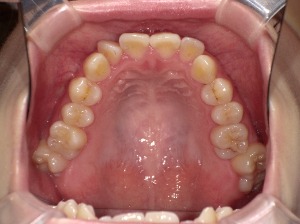

歯列の「アーチ形状」とは?

歯列のアーチとは、上・下の歯が並んでいるカーブの形のことです。

上から見たとき、歯が半円状に並んでいる様子をイメージしてください。

🔸 主な歯列アーチのタイプ

| U字型(広め) | 丸みのある緩やかなカーブ | 歯列が広く、笑顔が明るく見える |

| V字型(狭め) | 尖った形 | 顎が細く見えるが、口元が窮屈な印象に |

| スクエア型 | 前歯が直線的 | 男性的でシャープな印象 |

| 楕円型 | 自然でバランスの良い形 | 多くの人の理想的な歯列形状 |

アーチ形状は、顎の骨の形・歯の大きさ・舌の位置・筋肉の使い方などによって決まります。